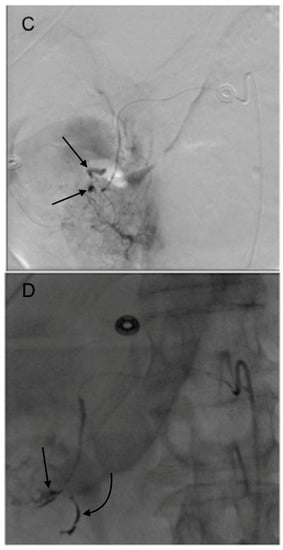

3. GDA Embolization in Gastrointestinal Bleeding

4. GDA Pseudoaneurysm Embolization